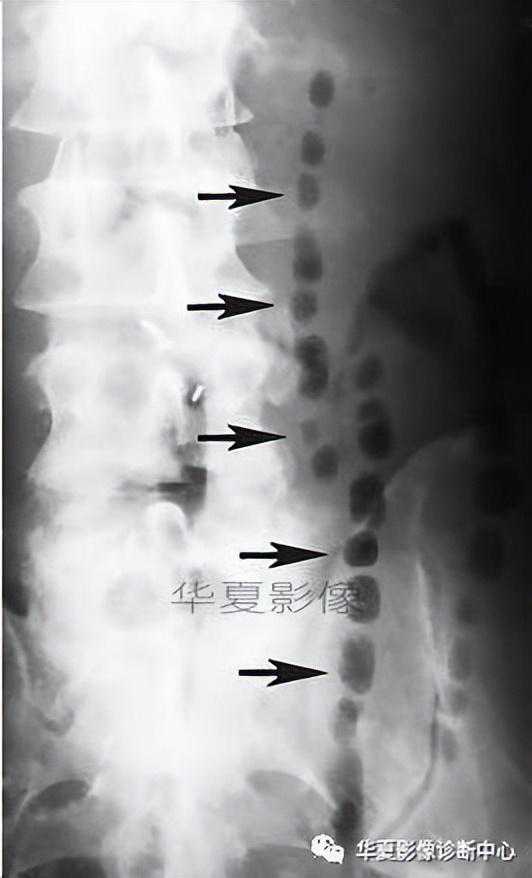

【影像表现】在小肠钡剂检查中,小肠形成类似于粗糙棉线一样的细钡线。

【征象解析】胃肠道严重狭窄,导致内腔呈线样改变,胃肠细绳征经常作为内腔狭窄的一个术语,但它最初用于描述克罗恩病的可逆性狭窄。狭窄原因是由于严重溃疡引起易激和痉挛所致的不完全性梗阻,且可以发现狭窄与扩张交替口当狭窄主要由水肿和痉挛引起时,狭窄程度不是一致的;如果小肠壁因纤维化而增厚,肠腔的内径就一致变窄。黏膜被纤维坏死组织所替代,偶尔黏膜岛仍可被发现。

【讨论】胃肠细绳征己被证实为克罗恩病的特征性表现,最常出现在末段回肠。

早期克罗恩病的肠道异常包括粗绒毛征、皱襞增厚和阿弗他溃疡。这些征象不是特异性的,也能在其他疾病中发现,但它们的出现能提供克罗恩病的坚实的证据。沿着肠系膜缘的线样溃疡成为小肠克罗恩病最重要的诊断特征之一,溃疡平行于短缩的、凹入的或者僵直的肠系膜缘。相邻的肠系膜增厚和回缩,特别在与有受侵肠段的连接处。坚硬的肠系膜缘是因为从线性溃疡扩散进人肠系膜形成透壁炎症。随着溃疡的进展,痉挛和易激加重,皱襞变得更粗糙和增厚,胃肠细绳征可以出现。根据病变的发展阶段不同,肠道近端可有或无扩张,痉挛经常是变化无常的,反复地观察照片证实在病变肠段有时会出现扩张。然而,当痉挛持久不变时,可发生暂时的近端肠管扩张并伴有肠梗阻症状。在狭窄期,继发于溃疡的痉挛导致持续的近端扩张,尽管狭窄和完全性肠梗阻罕见。除克罗恩病外,其他疾病也可出现类似征象。在幽门狭窄的病例中,窄的伸长的幽门管内部表现为单一的钡线口如果肠腔变窄和部分梗限出现,类癌也可导致胃肠道线样征的放射学表现。

总之,胃肠细绳征的出现高度提示克罗恩病,但它也可在其他疾病中出现。

左图:克罗恩病X线小肠钡灌,病变肠腔不规则狭窄(箭头),段壁僵硬,呈节段性分布;右图:CT横断位示小肠肠壁节段性增厚,肠腔狭窄(细白箭)